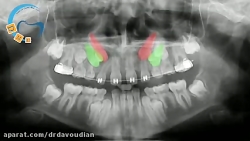

هدایت نیش نهفته در ارتودنسی | دکتر مسعود داوودیان